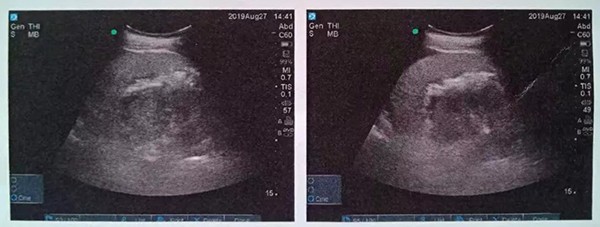

術中,泌尿外科郭駿博士精心設計手術通道,只在患者體表鉆出兩個0.5厘米的小洞,由于患者右側上位腎位置高,靠近肝臟和肺下葉,容易出現(xiàn)肝臟和肺的損傷,在B超的引導下精確穿刺腎結石的最高點,逐級擴張后建立皮腎通道。這時屢次“惹禍”的腎結石清楚的顯露在手術屏幕上,結石呈淺黃色,表面覆蓋淺褐色的膿苔,然后使用鈥激光將結石擊碎后取出。歷時一個半小時,結石全部清除,手術結束。